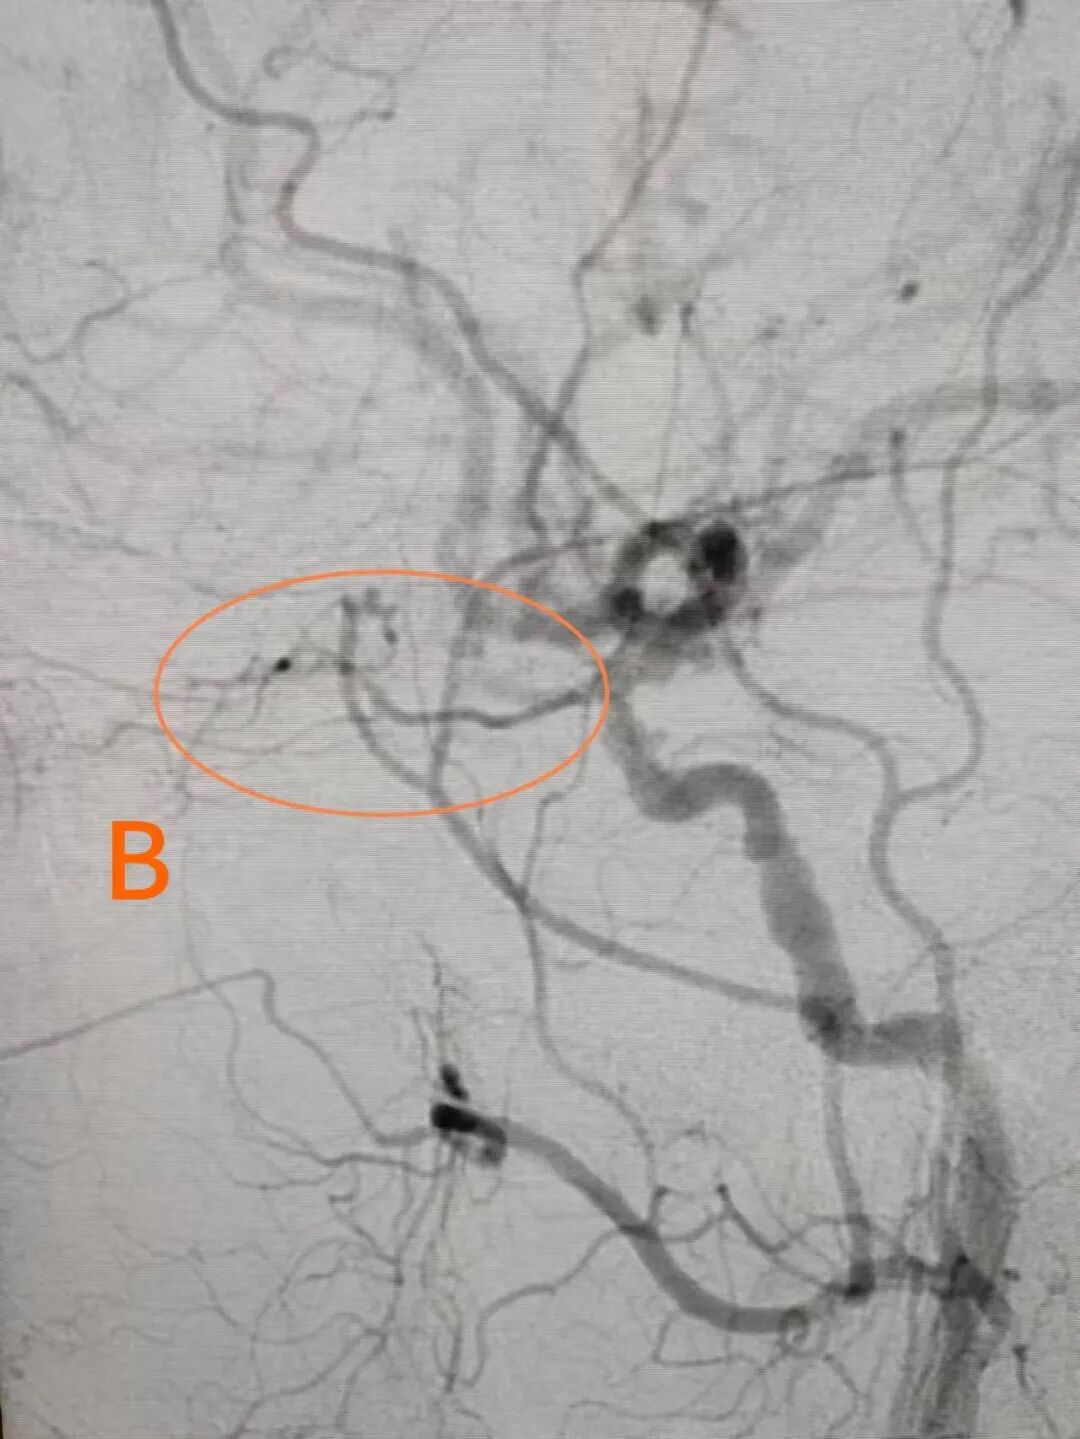

溶栓后见眼动脉显影